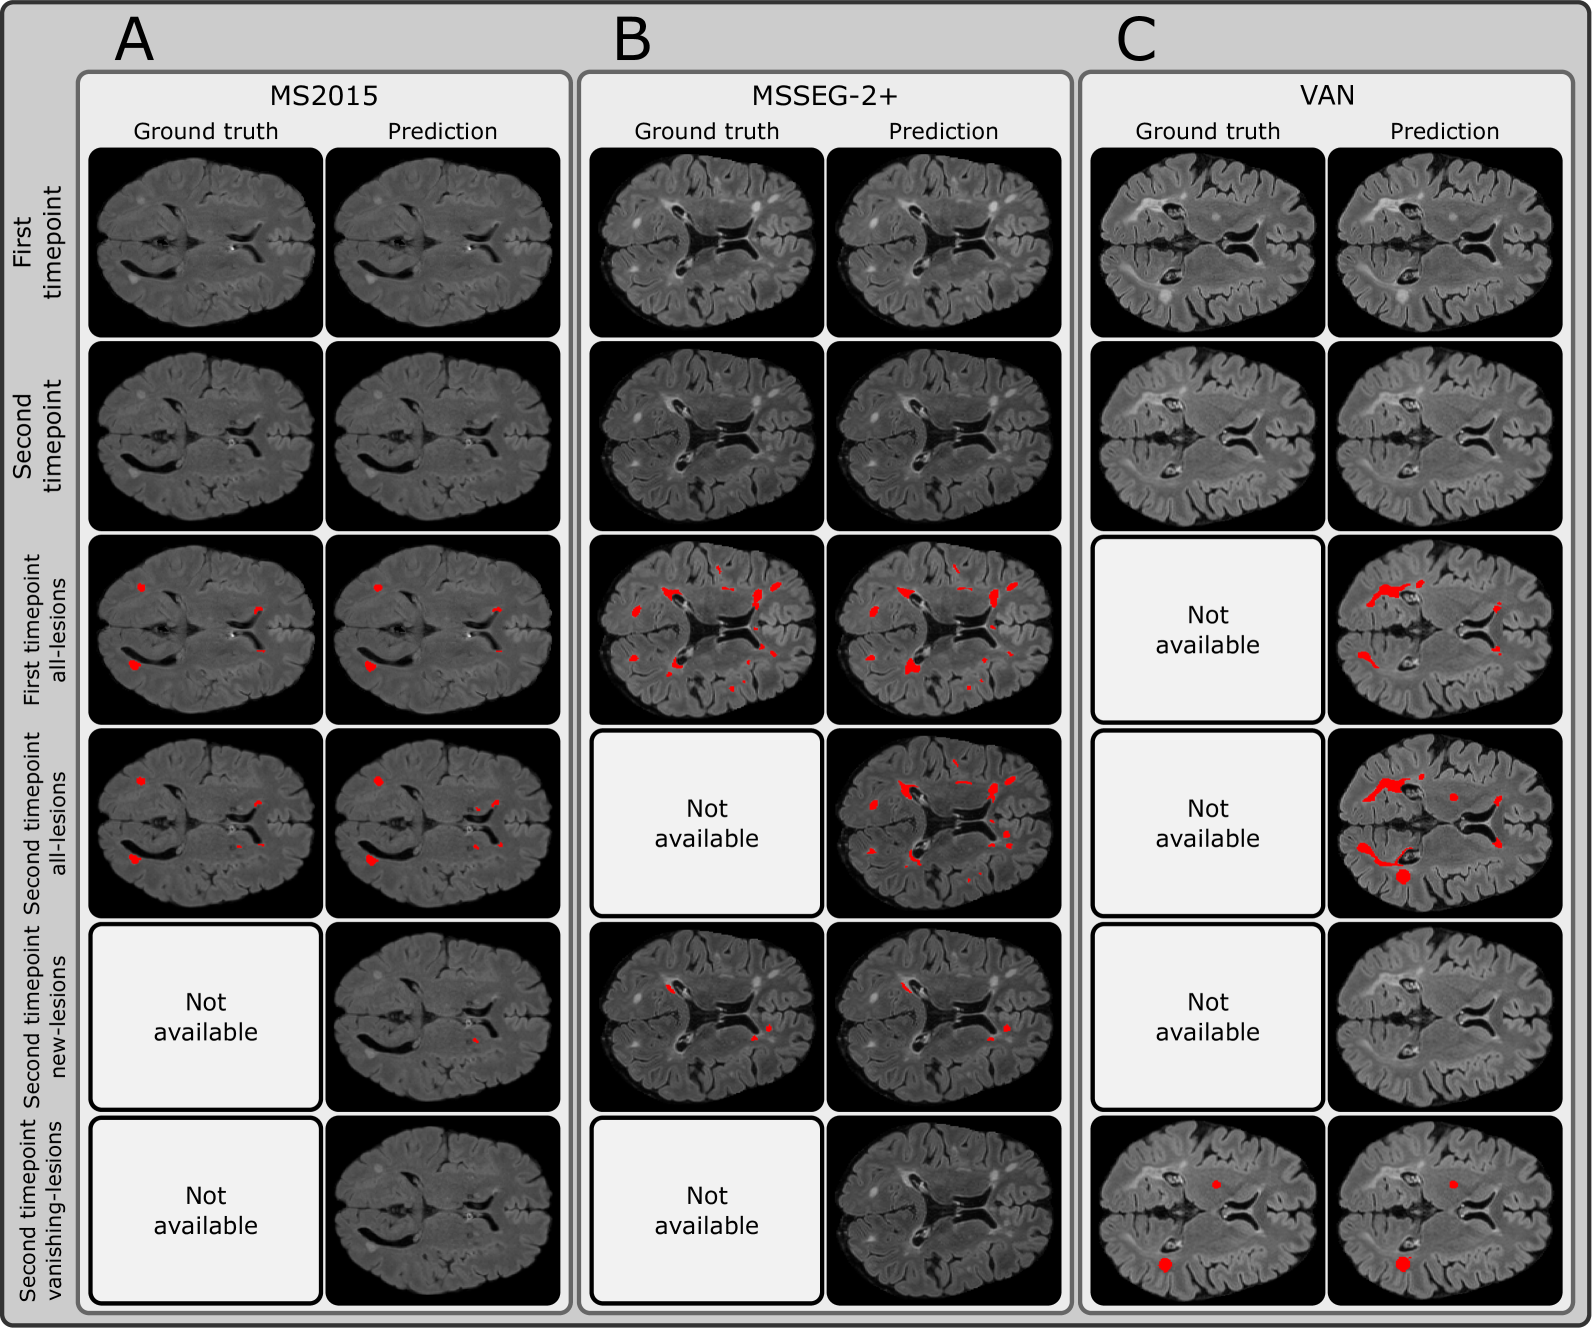

SegHeD is a unified model that can perform all-lesion, new-lesion, and vanishing-lesion segmentation tasks. We evaluate its multi-task performance and compare it against state-of-the-art (SOTA) task-specific segmentation methods, nnU-net [18], nnFormer [34], UNETR [15], a recent heterogeneous data learning method, CoactSeg [30], and specifically designed new-lesion segmentation methods [33, 1], shown in Table 2. Task-specific SOTA methods are trained twice, once for all-lesion segmentation task (using MS2015 and MS2016) and once for new-lesion segmentation task (using MSSEG-2). It is not possible to include the MSSEG-2+dataset into SOTA training, as these methods do not allow for the heterogeneous annotations which MSSEG-2+ possess. CoactSeg [30] is only trained once. For new lesion segmentation on MSSEG-2, we report Dice scores of MedICL [33], Basaran [1], and the average score of 4 human experts, Avg. of Experts, officially released by the challenge organisers [7], and include the lesion-wise F1𝐹1F1italic_F 1 scores in Table 3, in accordance with the MSSEG-2 challenge. Exemplar segmentations are compared in Figure 2, and further provided in Figure 3.

Figure 3: SegHeD is capable of simultaneous multi-task segmentation (Rows 3 to 6). Some tasks do not show new/vanishing-lesions predictions as they are not present at the given slice. "Not available" denotes no ground truth annotation for comparison. A: Dataset where all-lesion labels are available for first and second timepoints. B: Dataset where first timepoint all-lesion label and second timepoint new-lesion label are available. C: Dataset where second timepoint vanishing-lesion label is available.